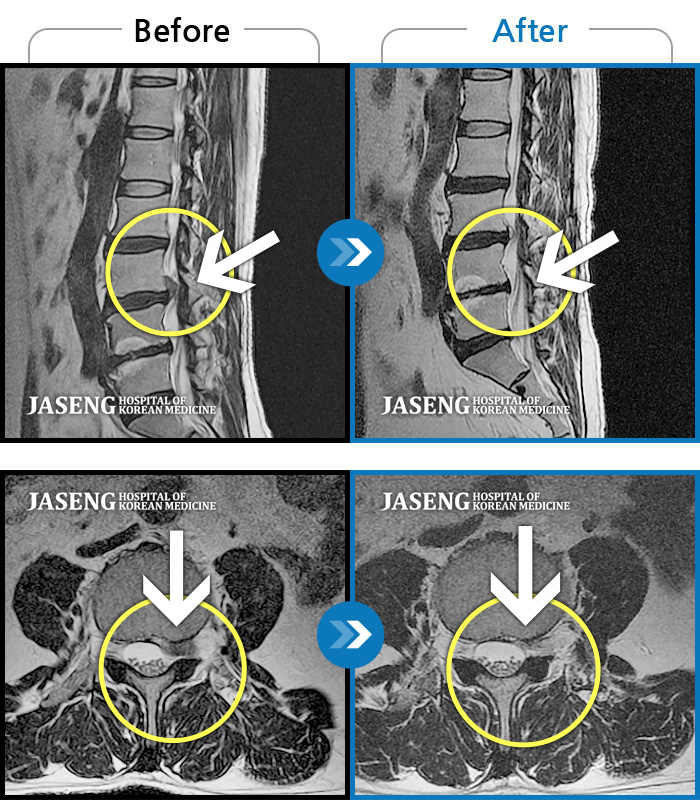

2년전 넘어지며 오른쪽 팔의 통증으로 병원을 찾고 있을때 지인의 소개로 김태용 원장님을 소개받고 자생한방병원 일산점을 찾게 되었습니다. 저는 단순 상해로 알고 있었지만 원장님께서는 목디스크로 진단하시고 보다 근본적인 통증원인을 찾으시고 시기적절한 처방과 치료를 받고 지금껏 불편함 없이 잘 지내고 있었습니다.

25년 1월 허리통증이 시작되고 잠을 잘수도없고 걸을 수 없을만큼의 상태가 되었을때 다시 김태용 원장님께 진료를 받고 예전 허리수술의(4번5번)(3번4번)디스크탈출증 재발과 협착증의 진단을 받고 지금까지 기나긴 여정의 입원 치료를 하며 곧 퇴원을 앞두고 있습니다.

눈내릴때 입원하여 꽃피는 춘삼월에 퇴원을 하게 된거죠~ 입원기간이 길어지며 주변의 간섭도 늘어갔고 저 또한 힘들어 포기하고 싶을때도 있었지만 원장님의 따듯한 말과 매일 같이 세심하게 환자의 상태를 파악하고 숙련되고 정확한 침치료와 약처방으로 지금은 일상생활에도 무리가 없을정도로 많이 호전 되었습니다.